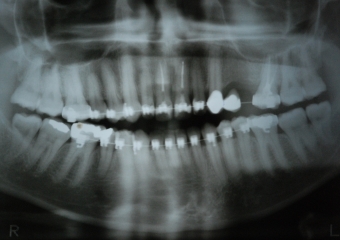

Imagens iniciais observando importante perda óssea e dentária superior

Raio X final